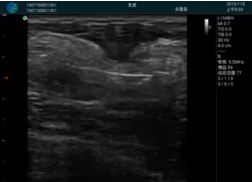

頸動脈血流充盈飽滿,無外溢

肝內血管顯示清晰,血流敏感無外溢

甲狀腺囊性結節(jié),囊壁鈣化,透聲好

甲狀腺囊性占位